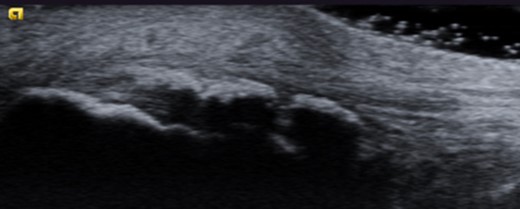

Dynamic ultrasound examination of the left heel showed a diffusely thickened subcutaneous bursa, with fluid-rich islands. Regions of high blood flow were seen in the bursal walls. There was tendinopathy in the distal Achilles, which measured 6–7 mm in thickness with intra-tendinous bone formations and calcification, but no high blood flow. Finally, there was a minor Haglund-like deformity with a sharp edge and a slightly enlarged retrocalcaneal bursa with the appearances of scar tissue formation, but no fluid or increased blood flow. There were no signs of partial ruptures in the distal part of the Achilles. These ultrasound findings were consistent with those of a previous MRI (Figs 1–5).

Ultrasound image of diffusely thickened subcutaneous bursa and underlying intra-tendinous bone formations.

Ultrasound image of minor Haglund deformity with sharp edge. Enlarged retrocalcaneal bursa with appearance of bursal scar tissue formation.